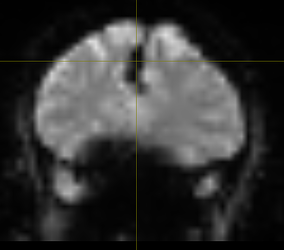

Which appears as a signal-void region, affecting LR_epi (one top) and RL_bold (two bottom) differently: